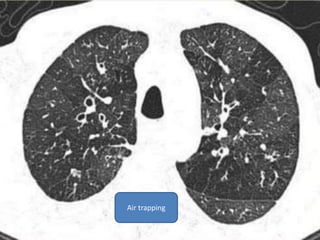

Heterogenous attenuation of lung parenchyma with ill defined low density areas of air

trapping peripherally

Air trapping